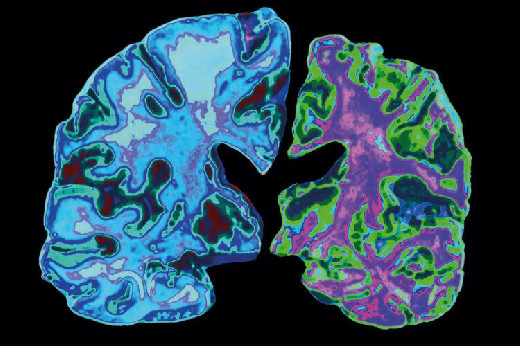

Модель с тремя маркерами показала стабильные результаты в независимых когортах и сохранила точность при тестировании на повторных образцах, взятых через несколько месяцев. В повторных образцах крови, собранных с интервалом в несколько месяцев, панель классифицировала состояние заболевания с точностью около 86% и отражала изменения диагностического статуса с течением времени. Структурный показатель также сильно коррелировал с результатами когнитивных тестов и в меньшей степени с показателями атрофии головного мозга, измеренными с помощью МРТ.

Иллюстрация к статье: